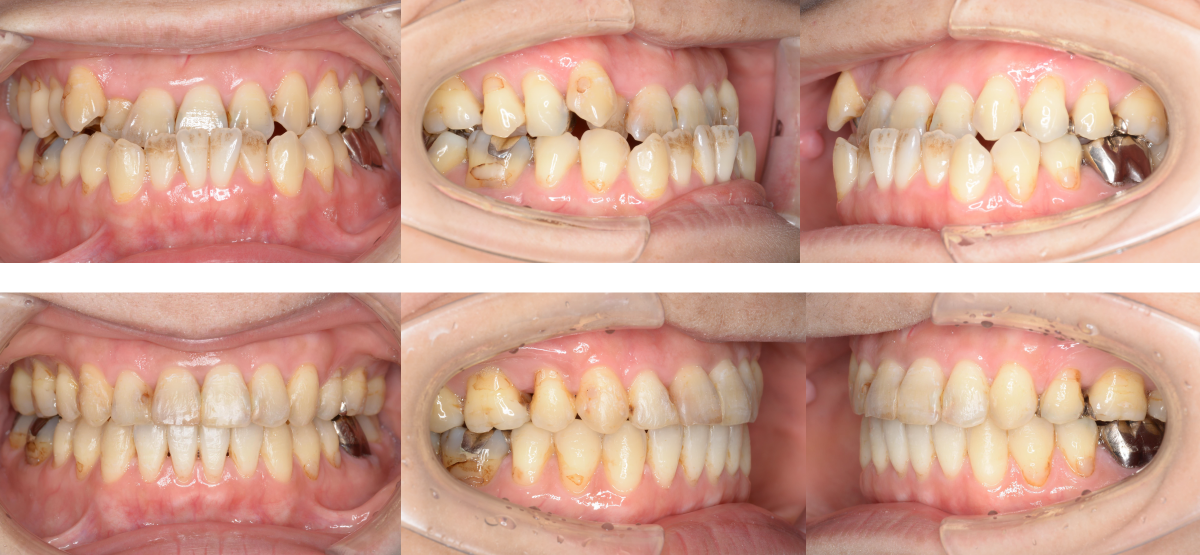

②顎矯正手術(外科矯正)の矯正治療例(30代女性・治療期間2年5か月)

| 年齢・性別 | 30代女性 |

| 治療期間 | 2年5か月 |

| 抜歯 | 上2本(小臼歯) |

| 治療費 | 100万円(調整費、保定費まで含む総額制) |

| 備考 | 裏側矯正 |

| リスク・副作用 | 痛み・治療後の後戻り・歯根吸収・歯髄壊死・歯肉退縮 |

横浜市からご来院の30代女性で、受け口(反対咬合)と交叉咬合(すれ違い)の症状がありました。

治療法は裏側矯正(舌側矯正)で、治療期間は2年5か月です。

2本抜歯で矯正治療を行い、キレイな歯並びになりました。